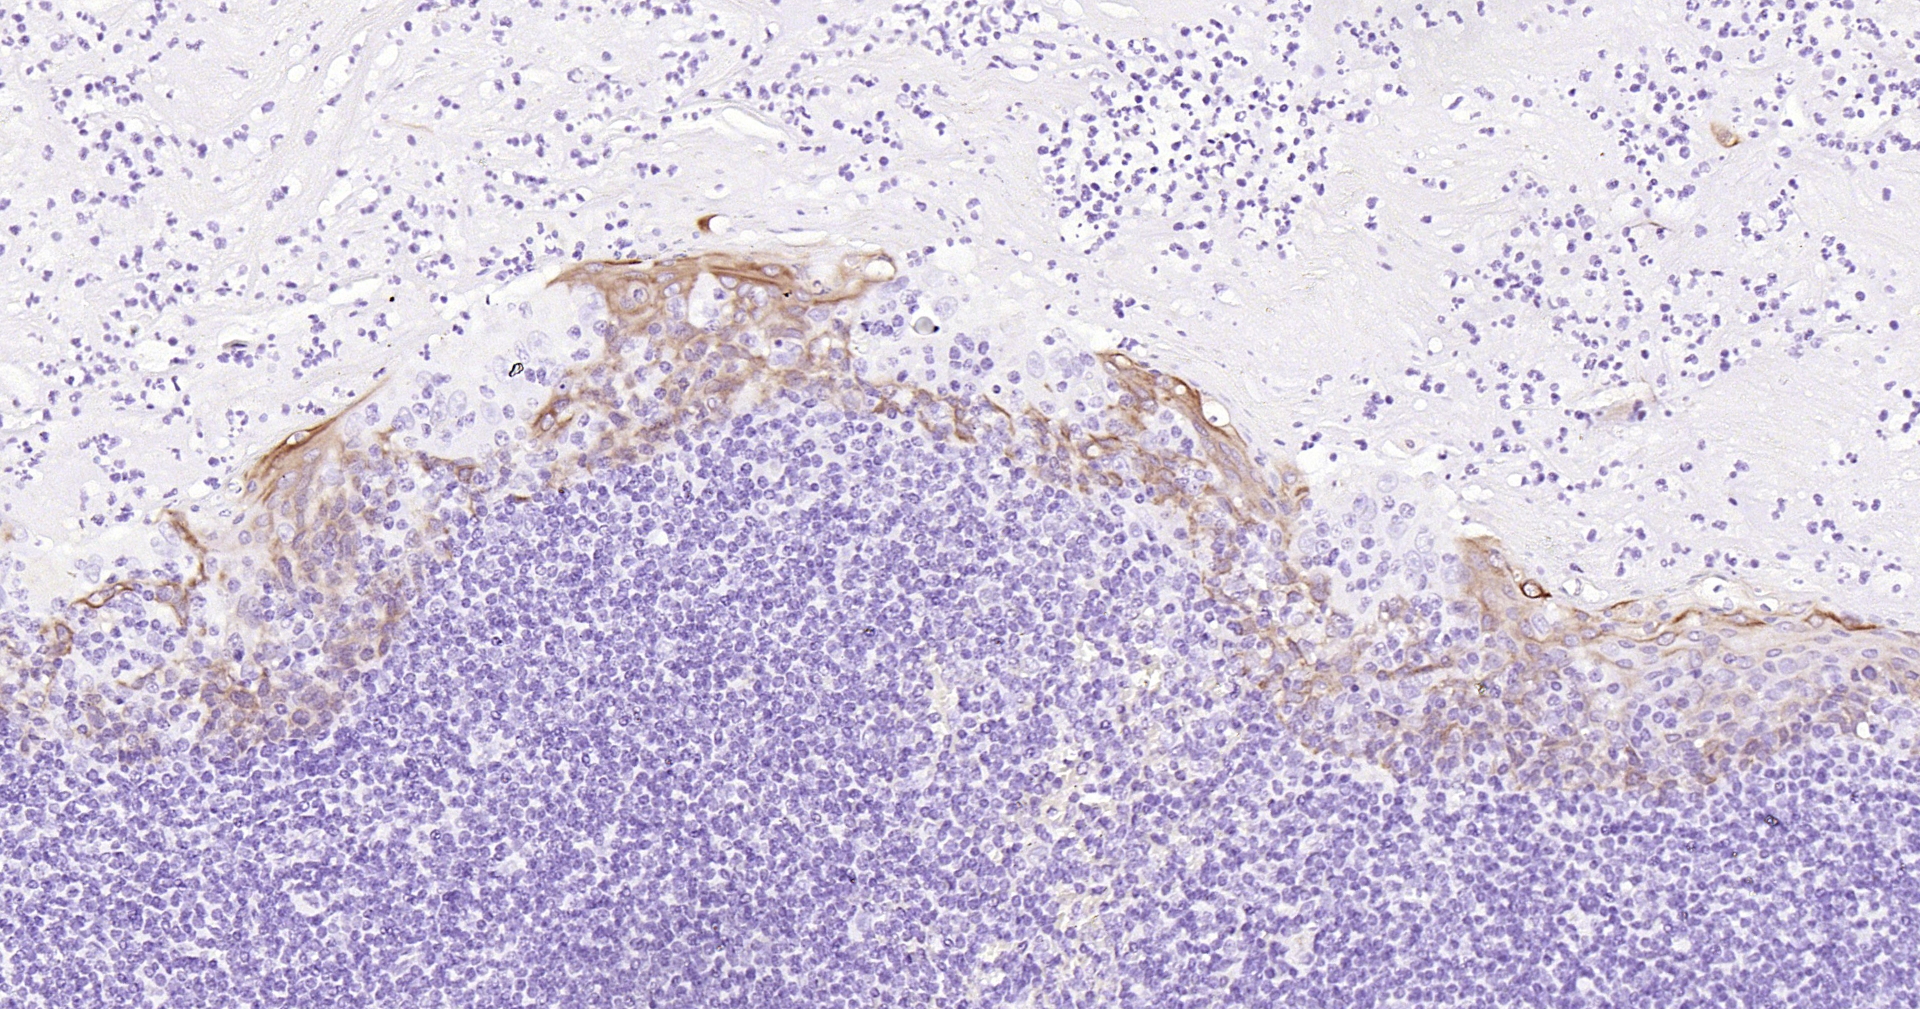

• IHC-P

IHC-P IHC-P1:100-500